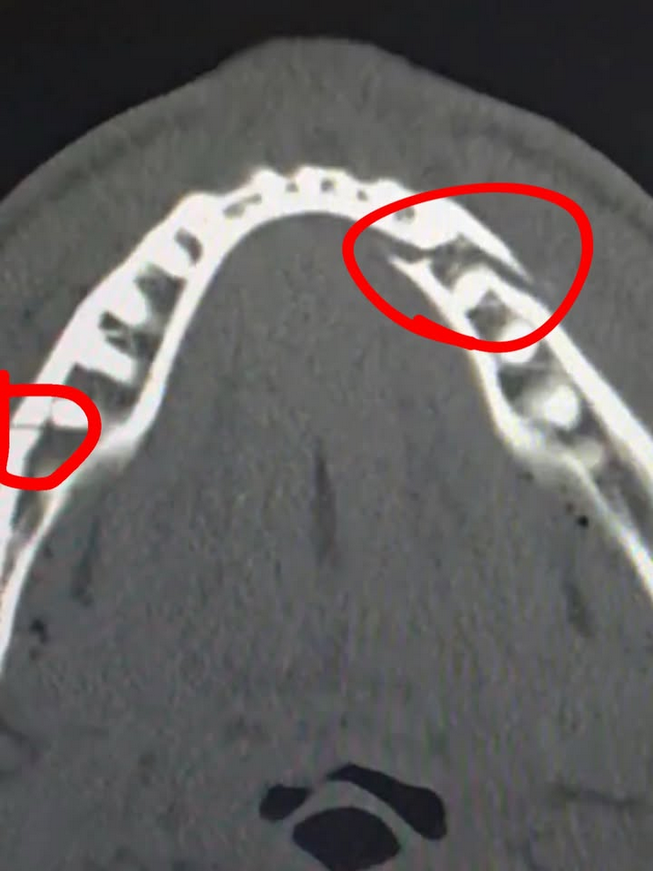

Jake Paul, who will spend at least seven days on a liquid diet, had to undergo surgery to have two titanium plates placed and several teeth removed.

“The surgery went well, thanks for all the love and support. Two titanium plates on each side. I had some teeth removed. I have to drink only liquids for seven days, so no Dog Haus,” shared the millionaire YouTuber.